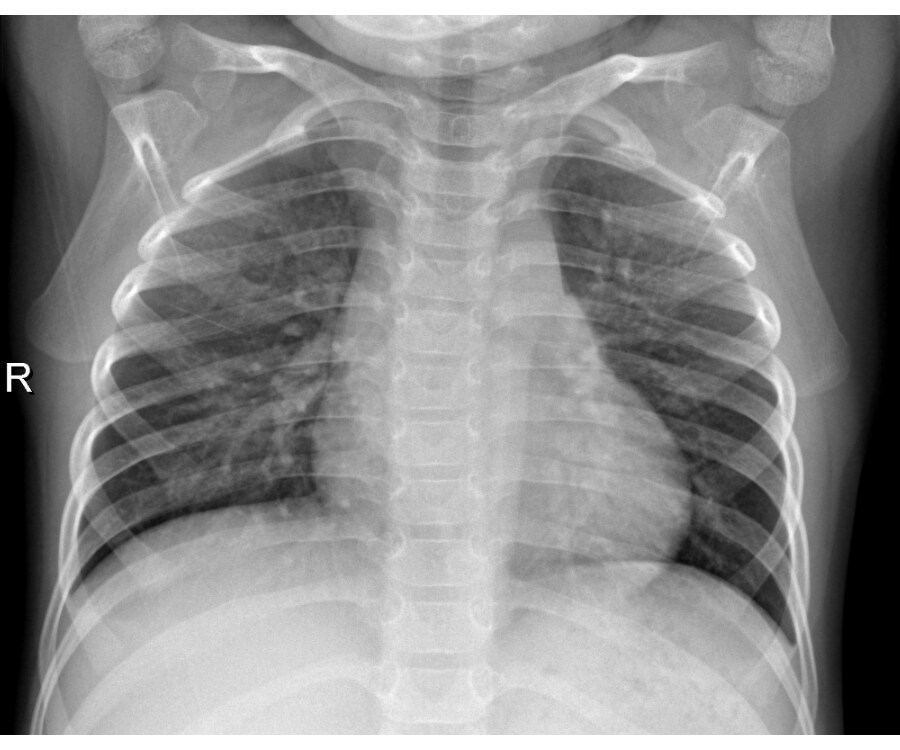

Chest X Ray In Pneumonia Chest X Ray Result For Pneumonia Your baby or young child has pneumonia; In hospital you'll usually be given fluids and antibiotics to treat the infection. While the physical exam can raise suspicion for pneumonia, the diagnosis can be strengthened using a variety of tests. Your healthcare provider may or may. Your doctor will start by asking about. 1.1 presentation with lower respiratory tract infection. A. Chest X Ray Result For Pneumonia.

Chest Xray Of A Year Old Female With Pneumonia Front View Stock Photo Chest X Ray Result For Pneumonia Your doctor will start by asking about. Your baby or young child has pneumonia; Your healthcare provider may or may. In hospital you'll usually be given fluids and antibiotics to treat the infection. A doctor can often diagnose pneumonia based on the symptoms and by checking your chest. 1.1 presentation with lower respiratory tract infection. While the physical exam can. Chest X Ray Result For Pneumonia.

Chest Xray of a Patient with Pneumonia Stock Photo Image of clavicle Chest X Ray Result For Pneumonia In hospital you'll usually be given fluids and antibiotics to treat the infection. Your baby or young child has pneumonia; Your healthcare provider may or may. While the physical exam can raise suspicion for pneumonia, the diagnosis can be strengthened using a variety of tests. A doctor can often diagnose pneumonia based on the symptoms and by checking your chest.. Chest X Ray Result For Pneumonia.

Pneumonia. Xray of the chest of a patient with bacterial pneumonia Chest X Ray Result For Pneumonia Your healthcare provider may or may. While the physical exam can raise suspicion for pneumonia, the diagnosis can be strengthened using a variety of tests. In hospital you'll usually be given fluids and antibiotics to treat the infection. 1.1 presentation with lower respiratory tract infection. Your baby or young child has pneumonia; Your doctor will start by asking about. A. Chest X Ray Result For Pneumonia.